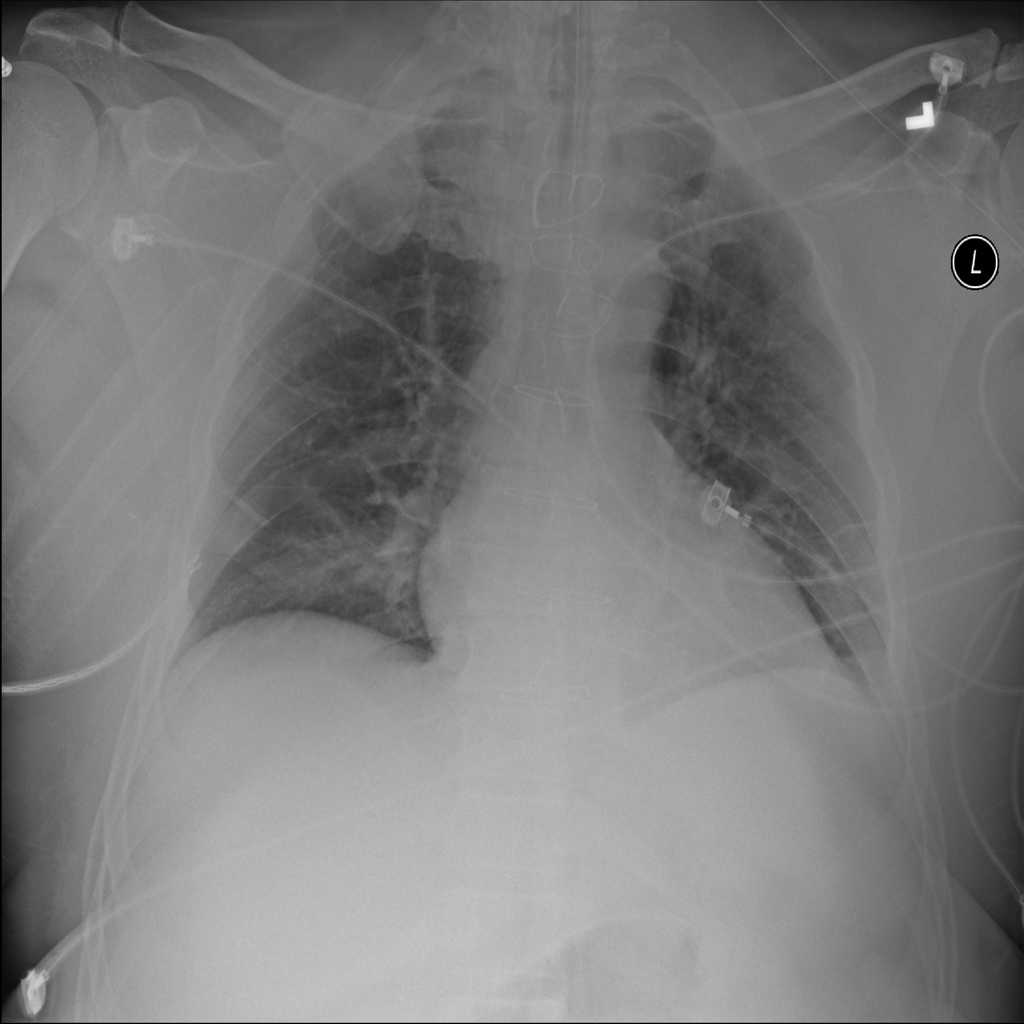

PAT-B625 · IMG-008Atelectasis

PAT-B625 · IMG-008

AP